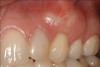

Fig 9. Seibert Class II defect in teeth Nos. 9 and 10 areas under tooth bridge Nos. 8 through 11 with pink porcelain to mask the loss of gum and bone (Fig 9). Soft-tissue ridge augmentation using tuberosity CTG was performed for implant bridge Nos. 8 through 11. Restorative treatment included a bridge from Nos. 8 through 11 with ovate pontics and crowns on Nos. 6 and 7 (Fig 10). The patient will have additional root coverage grafting in the future. Note there was no keloid-like appearance in this case, as the CTG was trimmed to fit the space precisely (restorative treatment completed by Todd D. Gruen, DDS).

Figure 9

Fig 10. Seibert Class II defect in teeth Nos. 9 and 10 areas under tooth bridge Nos. 8 through 11 with pink porcelain to mask the loss of gum and bone (Fig 9). Soft-tissue ridge augmentation using tuberosity CTG was performed for implant bridge Nos. 8 through 11. Restorative treatment included a bridge from Nos. 8 through 11 with ovate pontics and crowns on Nos. 6 and 7 (Fig 10). The patient will have additional root coverage grafting in the future. Note there was no keloid-like appearance in this case, as the CTG was trimmed to fit the space precisely (restorative treatment completed by Todd D. Gruen, DDS).

Figure 10

Depending on the 3-dimensional aspect of the graft, it can be adjusted in a myriad of ways for thickness and for the number of teeth receiving root coverage. If the CT is being used for a soft-tissue ridge-augmentation procedure, the tissue, of course, can be left thicker (Figure 7 through Figure 10). This prevents the need to suture multiple pieces of graft material together, which is commonly needed with other graft materials.